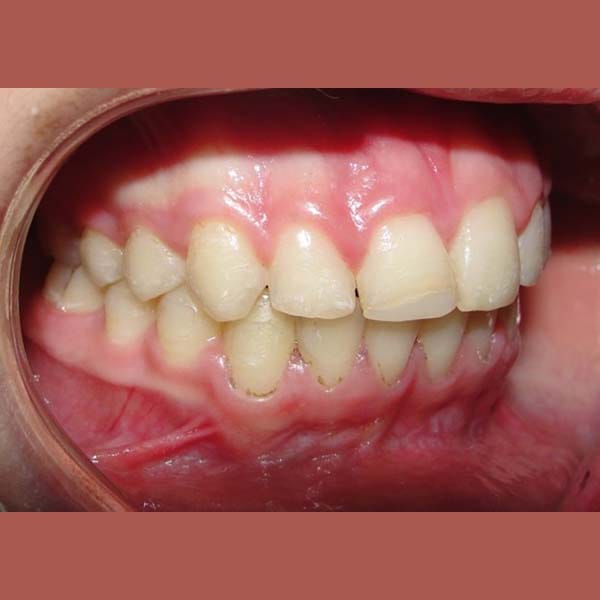

عانت هذه الفتاة الصغيرة من بروز شديد في الأسنان وصل إلى 1 سم، وكان سببه الرئيسي هو تراجع الفك السفلي، وهو ما كان يظهر بوضوح على بروفيل وجهها الجانبي.

كما تظهر الصور، كان التحسن جذرياً ليس فقط في الابتسامة ولكن في تناسق ملامح الوجه بالكامل. تم تصحيح البروز، وتحسنت علاقة الفكين، وحصلت صديقتنا الصغيرة على ابتسامة جميلة وواثقة.